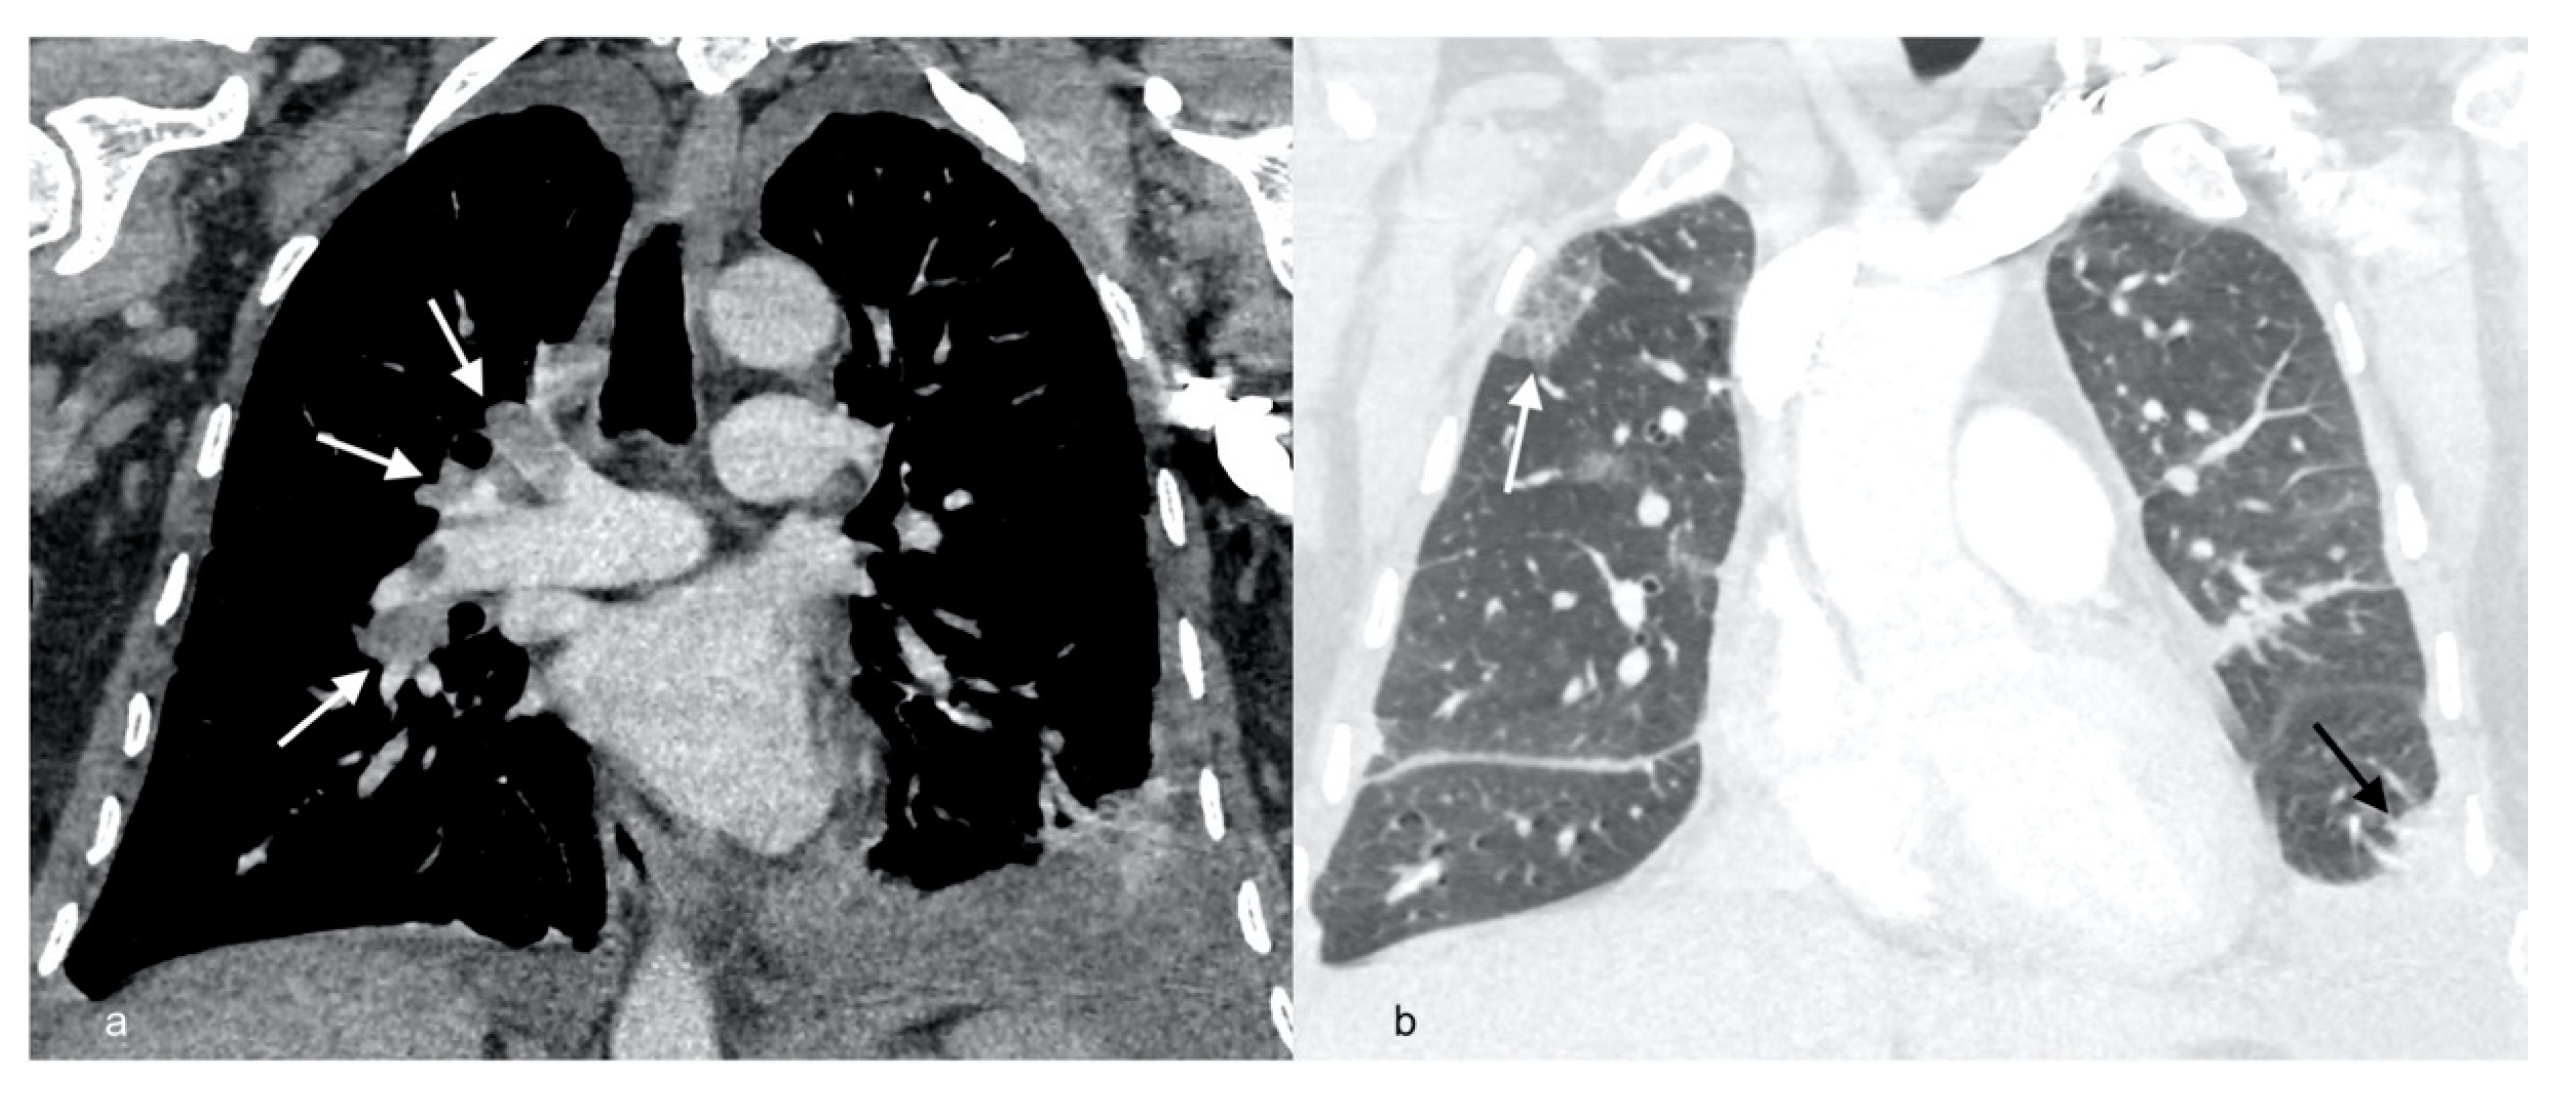

| Radiological picture | Pulmonary embolism, parenchymal infiltrates, bilateral pleural fluid | Regression of PA thrombi, pleural fluid and parenchymal consolidations | Complete resolution of PA thrombi, pleural fluid and lung consolidations | |